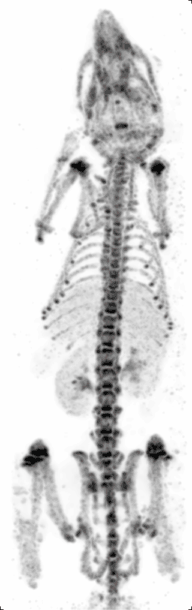

Micro-SPECT

Principle: Similar to PET, single photon emission computed tomography (SPECT) also images living systems through γ-rays emitted from within the subject. Unlike PET, the radioisotopes used in SPECT (such as technetium-99m) emit γ-rays directly,[8] instead of from annihilation events of a positron and electron. These rays are then captured by a γ-camera rotated around the subject and subsequently rendered into images.

Strengths: The benefit of this approach is that the nuclear isotopes are much more readily available, cheaper, and have longer half-lives as compared to micro-PET isotopes. Like micro-PET, micro-SPECT also has very good sensitivity and only nanograms of molecular probes are needed.[15] Furthermore, by using different energy radioisotopes conjugated to different molecular targets, micro-SPECT has the advantage over micro-PET in being able to image several molecular events simultaneously. At the same time, unlike micro-PET, micro-SPECT can reach very high spatial resolution by exploring pinhole collimation principle (Beekman et al.)[16] In this approach, by placing the object (e.g. rodent) close to the aperture of the pinhole, one can reach high magnification of its projection on detector surface and effectively compensate for intrinsic resolution of the crystal.

Weaknesses: Micro-SPECT still has considerable radiation which may affect physiological and immunological pathways in the small animals. Also, radiation may affect tumor size in cancer models as it mimics radiotherapy, and thus extra control groups might be needed to account for this potential confounding variable. Micro-SPECT can also be up to two orders of magnitude less sensitive than PET.[2] Furthermore, labeling compounds with micro-SPECT isotopes require chelating molarities which may alter their biochemical or physical properties.

Cancer research: Micro-SPECT is often used in cancer research for molecular imaging of cancer-specific ligands. It can also be used to image the brain because of its penetration power. Since newer radioisotopes involve nanoparticles such as 99mTC-labelled iron oxide nanoparticles, they could potentially be combined with drug delivery systems in the future.[14]